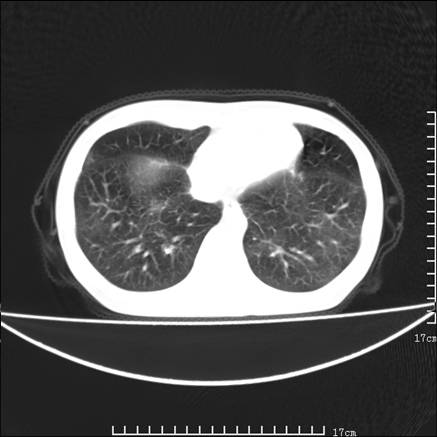

女,46岁,患胃溃疡多年,溃疡大小约1.0cm左右,后于5年前手术,病理为胃癌。主诉:半月前感冒后胸闷,气短,有咳嗽,无明显咳痰,无发热。偶有腰背部不适。

以下为高分辨扫描图像

双肺小叶间增厚,双肺散布粟米影和磨玻璃状影,以双肺上叶为重。结合病史考虑转移(癌性淋巴细管炎)可能性大。

结合病史:认为是典型肺部癌性淋巴管炎、淋巴结转移。请看图解。

肺癌性淋巴管炎征象分为主要征象及合并征象,主要征象包括:

1、近肺门支气管血管周围间质结节状增厚;

2、小叶间隔结节状增厚;

3、小叶中央间质结节状增厚;

4、胸膜下间质结节状增厚。

合并征象为:纵隔淋巴结增大,胸腔积液,肺多发随机分布的小结节等。